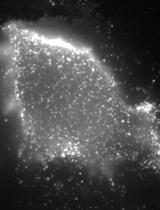

Figure 1. p-SMAD2 staining (arrowhead) in liver metastasis generated after intrasplenic injection of CRC cells. E: epithelial cells, Str: stromal cells. Scale bars = 10 μm